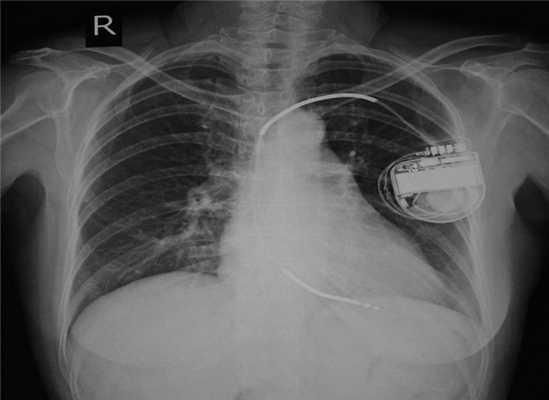

Если у больного имеется имплантированный кардиостимулятор или кардиовертер-дефибриллятор

При дефибрилляции, кардиоверсии у пациентов с имплантированными электрокардиостимуляторами электроды обычно устанавливают в передне-заднем или передне-боковом положении. Не стоит располагать электрод непосредственно над имплантированным устройством. Стараются выбрать такую позицию, чтобы расстояние между электродами и кардиостимулятором было > 8 см. После проведенной процедуры проводят проверку работы кардиостимулятора или кардиовертера-дефибриллятора.